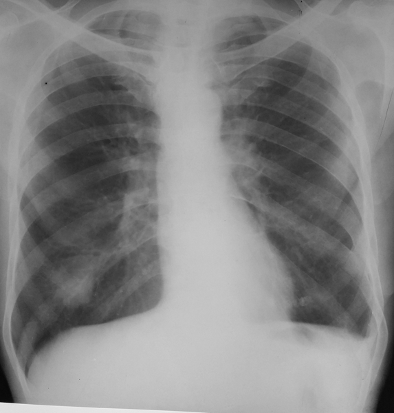

Rx toracică, incidență P-A

DESCRIERE:

pe tot teritoriul pulmonar, bilateral → opacități nodulare multiple de dimensiuni variabile, intensitate medie-mare, omogene, cu contur net

distribuție anarhică

blocuri adenopatice la niv. hilurilor pulmonare

DX: MTS pulmonare hematogene

DD:

hidatidoză - dimensiuni mai mari

bronhopneumonie - contur neregulat, neomogene, distribuție bazală